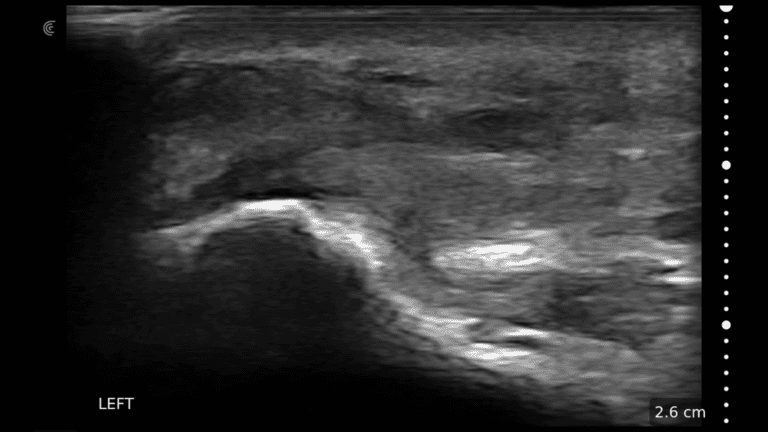

A survey scan of the elbow can identify some of the most common pathologies that cause acute and chronic elbow pain such as tendinosis of the common flexor or extensor tendons, joint effusion, or olecranon bursitis.